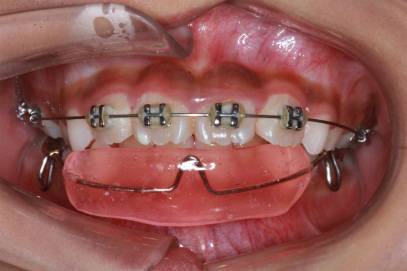

照相:包括口外像和口内像。这些照片不仅是医生诊断和制定矫治方案的重要依据,同时也是治疗前后进行对比的重要资料。

口外照像(上)和口内照像(下)